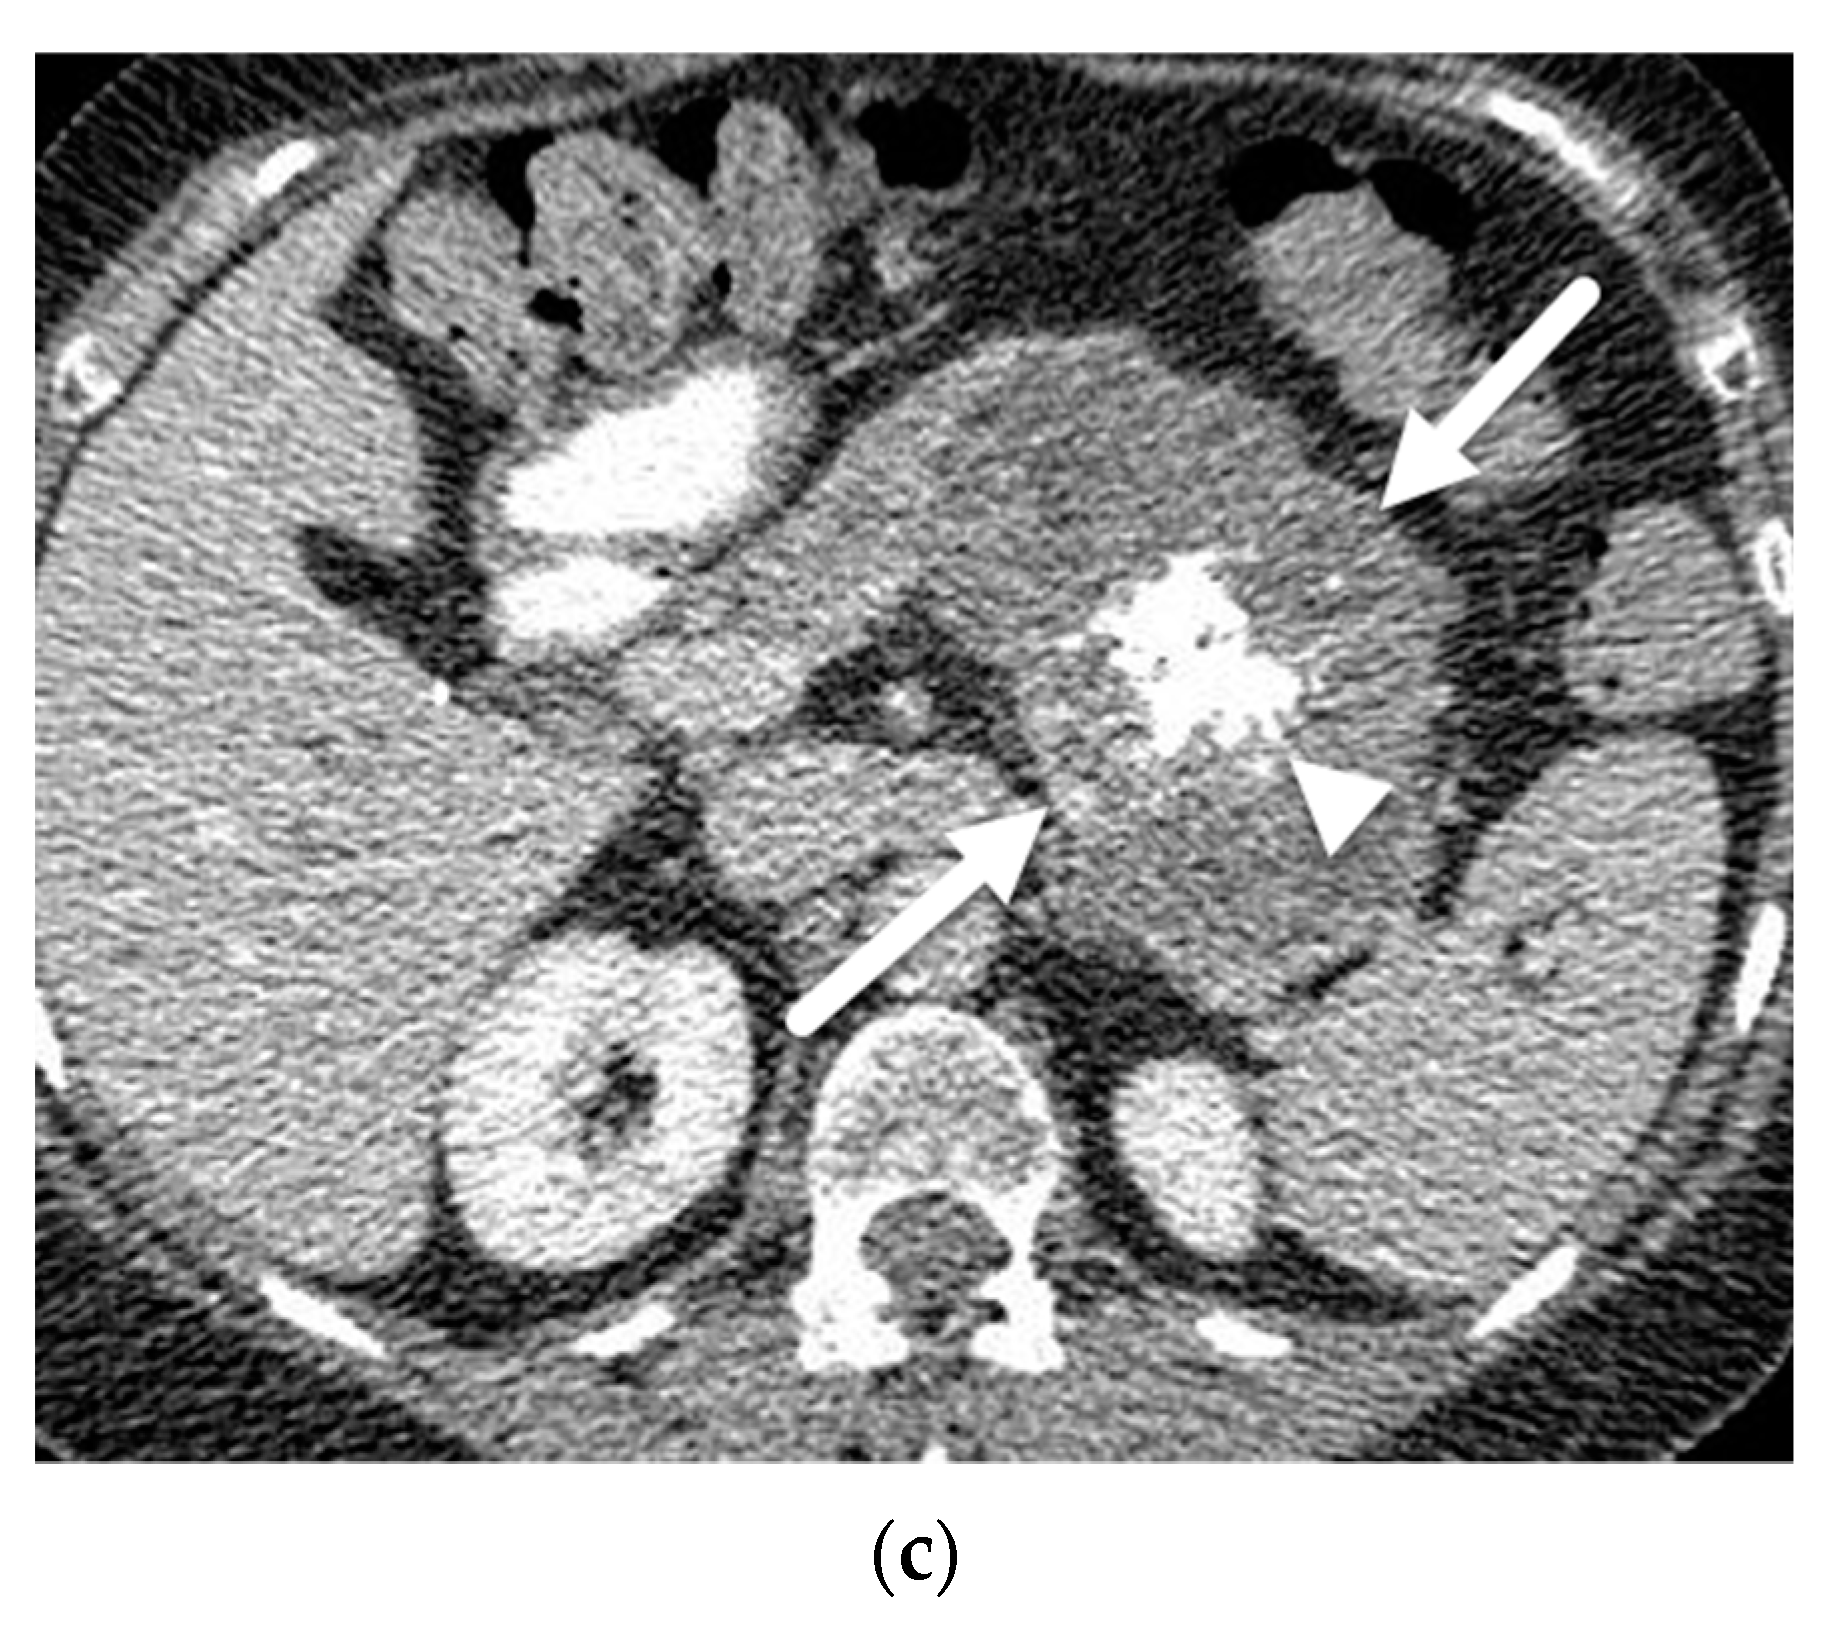

- Mamone, G.; Barresi, L.; Tropea, A.; Di Piazza, A.; Miraglia, R. MRI of mucinous pancreatic cystic lesions: A new updated morphological approach for the differential diagnosis. Updates Surg. 2020, 72, 617–637. [Google Scholar] [CrossRef] [PubMed]